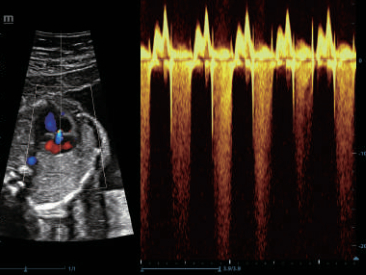

–Γ–Ω–Β―Ü–Η–Α–Μ―¨–Ϋ–Ψ ―¹–Κ–Ψ–Ϋ―¹―²―Ä―É–Η―Ä–Ψ–≤–Α–Ϋ–Ϋ―΄–Ι –¥–Α―²―΅–Η–Κ –¥–Μ―è –Ω―Ä–Ψ–≤–Β–¥–Β–Ϋ–Η―è –Η–Ϋ–≤–Α–Ζ–Η–≤–Ϋ―΄―Ö –Ω―Ä–Ψ―Ü–Β–¥―É―Ä –Η –Η―¹―¹–Μ–Β–¥–Ψ–≤–Α–Ϋ–Η–Ι –≤ 2D ―¹ –Φ–Η–Ϋ–Η–Φ–Α–Μ―¨–Ϋ–Ψ–Ι ―¹–Μ–Β–Ω–Ψ–Ι –Ζ–Ψ–Ϋ–Ψ–Ι, –Α ―²–Α–Κ–Ε–Β –Κ–Ψ–Ϋ―²―Ä–Α―¹―²-―É―¹–Η–Μ–Β–Ϋ–Ϋ―΄―Ö –Η―¹―¹–Μ–Β–¥–Ψ–≤–Α–Ϋ–Η–Ι;

–ï–≥–Ψ –Κ–Ψ―Ä–Ω―É―¹ ―É–¥–Ψ–±–Ϋ–Ψ ―Ä–Α–Ζ–Φ–Β―â–Α–Β―²―¹―è –≤ ―Ä―É–Κ–Β –Η –Ω–Ψ–¥–¥–Β―Ä–Ε–Η–≤–Α–Β―² –Ω―Ä–Η–Φ–Β–Ϋ–Β–Ϋ–Η–Β ―¹–Ω–Β―Ü–Η–Α–Μ–Η–Ζ–Η―Ä–Ψ–≤–Α–Ϋ–Ϋ–Ψ–Ι –±–Η–Ψ–Ω―¹–Η–Ι–Ϋ–Ψ–Ι –Ϋ–Α―¹–Α–¥–Κ–Η ―¹ –Ω–Ψ–Κ―Ä―΄―²–Η–Β–Φ –Η–Ζ –Ϋ–Α–Ϋ–Ψ–Φ–Α―²–Β―Ä–Η–Α–Μ–Α –¥–Μ―è –Μ–Β–≥–Κ–Ψ–Ι –¥–Β–Ζ–Η–Ϋ―³–Β–Κ―Ü–Η–Η.